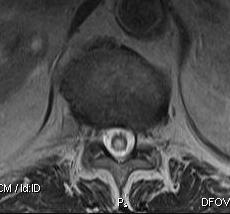

MRI

Most sensitive investigation

- main differential is oedema

- need T1 image

Pathology

Cord damage

- anterior dissection of cavity with interruption of decussating spinothalamic fibres

- effects pain & temperature

- extension into lateral corticospinal tracts

- fluid-filled tubular cavity

- separate from but usually communicating with central canal

Cystic space

- lined by thick layer of glial tissue

- gliosis with tendency to infiltrate white matter